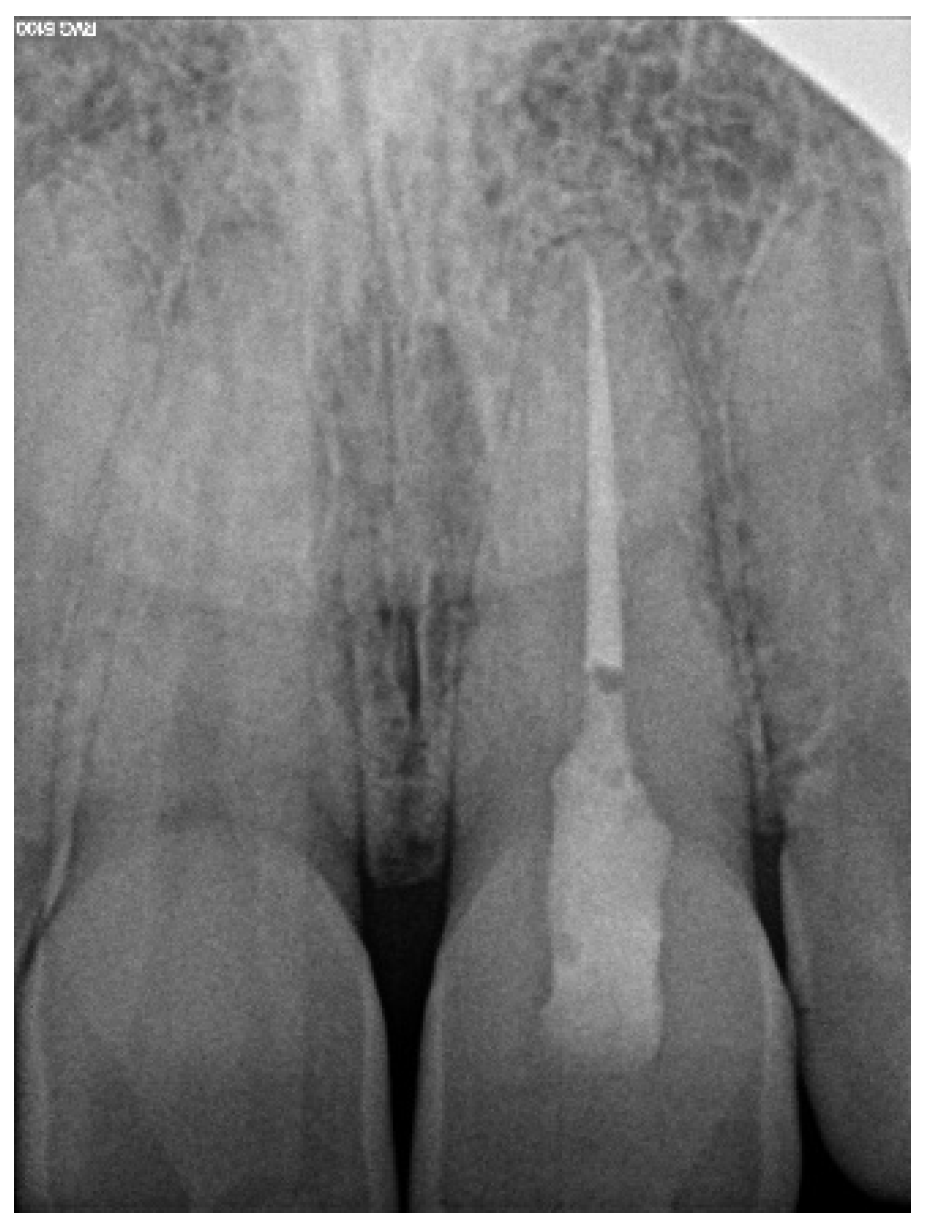

2.2. Canal Calcification in Elderly Patients

2.2.1. Case Report—Patient C: Asymptomatic Pulp Canal Obliteration—Endodontic Treatment before Surgical Procedure

Three-Dimensional Treatment Plan and RCT